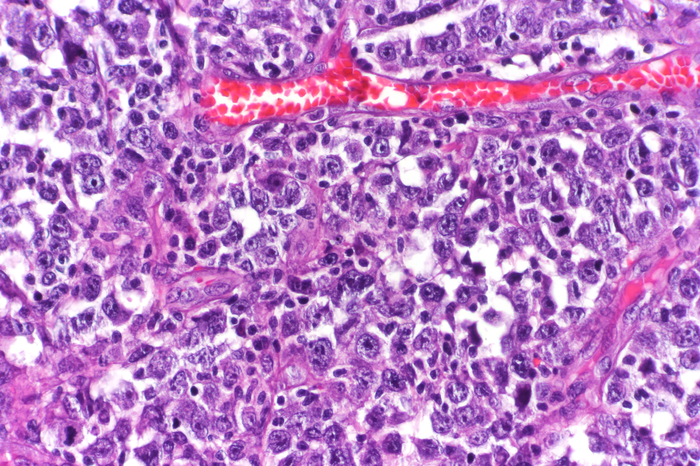

Diffuse large B-cell lymphoma (IMAGE)